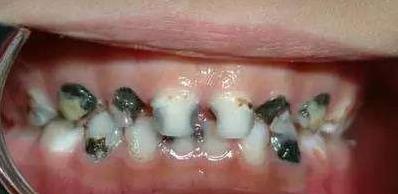

*四环素牙:在牙发育矿化期,服用的四环素族药物,可被结合到牙组织内,使牙着色。也可导致牙釉质发育不全从而导致牙齿变色。(四环素在牙本质内,因结合部位的深浅而使牙本质着色的程度有所不同,当着色带越靠近釉牙本质界时,越易着色,因而在婴儿早期形成外层牙本质时,用药影响最大。)

*氟斑牙:氟主要损害牙釉质发育期牙胚的造釉细胞,因此,过多的氟只有在牙发育矿化期进入机体,才能发生氟牙症(六七岁之前,避免儿童在高氟地区)

临床上常按其轻、中、重度而分为白垩型(轻度)、变色型(中度)和缺损型(重度)三种类型。